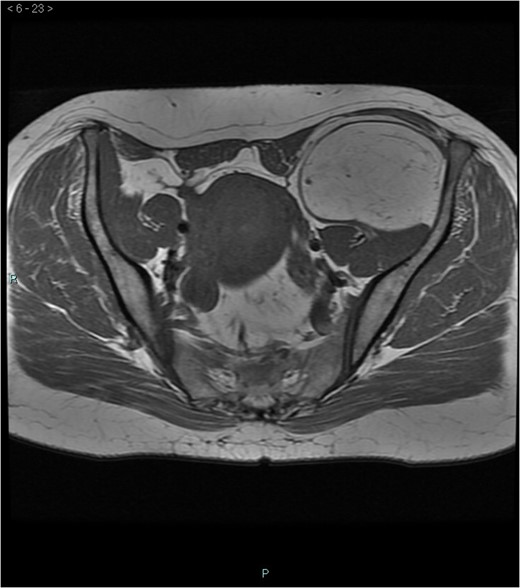

A 58-year-old woman was evaluated for lower abdominal pain, without additional symptoms. An abdominal ultrasonography revealed the presence of a 15 cm homogenous mass, located in the left pelvic cavity. Subsequent MRI showed a capsulated mass, isointense with the adipose tissue, longitudinally extending from the left inguinal area to the left leg root and located on the medial aspect of the left iliac bone. MRI also revealed within the mass some fibrotic branches containing small blood vessels. No evidence of extracapsular invasion of the surrounding structures was evident (Figs 1–6).

Preoperative differential diagnosis is mainly based on radiologic imaging and is very difficult, because no pathognomonic signs exists for diagnosis of hibernoma; usually CT-scan shows an homogenous lesion, whose density is between subcutaneous fat and skeletal muscle; MRI shows slightly lower signal intensity on T1 weighted spin-echo (T1WSE), marked enhancement and partial fat suppression on short Tau inversion recovery (STIR) and fat-saturated sequences [5].